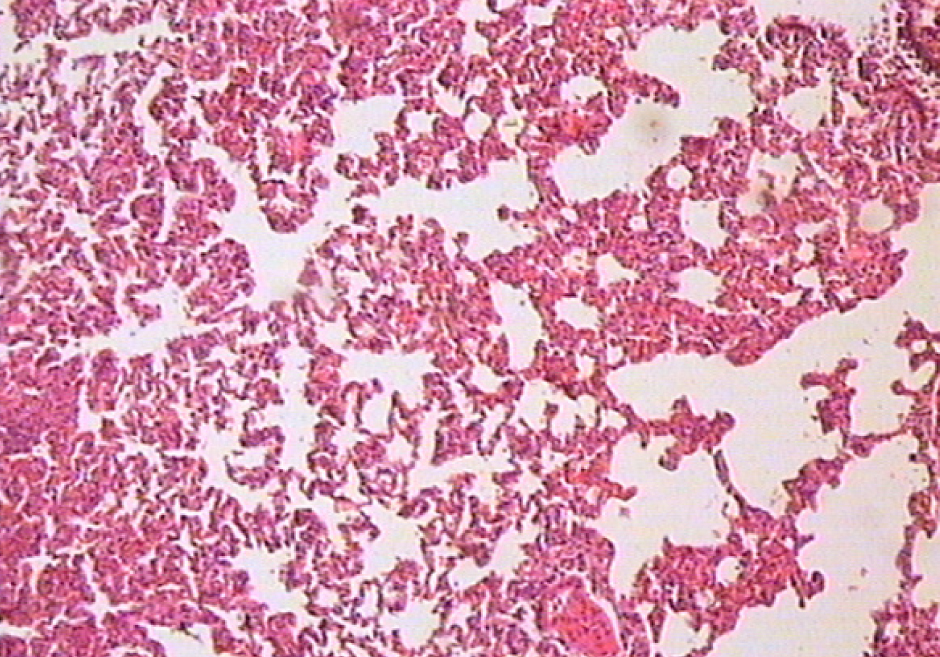

При исследовании гистологических срезов в легких определяются безвоздушные участки, чередующиеся с эмфизематозно расширенными (рис. 1).

Рис. 1. Безвоздушные участки легкого, чередующиеся с эмфизематозно измененными. Окраска гематоксилином и эозином. Ок. 10. Об. 4